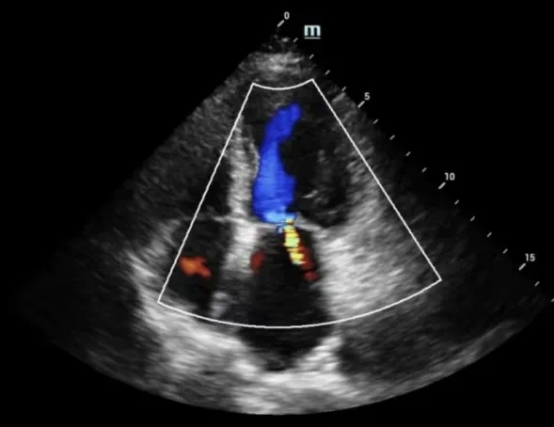

心脏彩超即超声心动图,是利用现代电子技术和超声原理,在人体外直接测查心脏大小、心肌厚度、瓣膜形态、血液流动、心包状态,进而研判心脏功能的检查技术,指导临床早干预、早治疗一一具有经济、无创、重复性强的特点,已成为辅助心脏科提高检查效率不可缺少的手段,常常被誉为心脏科医生的"第三只眼"。

心电图、心脏超声均是目前用于心脏疾病实施检查与诊断的常用方法。心脏彩超和心电图两者则是相辅相成,互不可缺的。打个比喻,心脏就好比是4居室屋子,心脏彩超看屋子有多大,墙结不结实,门严不严实,漏不漏水;心电图则是看电路通不通,有没有短路、漏电,所以房屋的好坏要看结构及电路是否正常的。